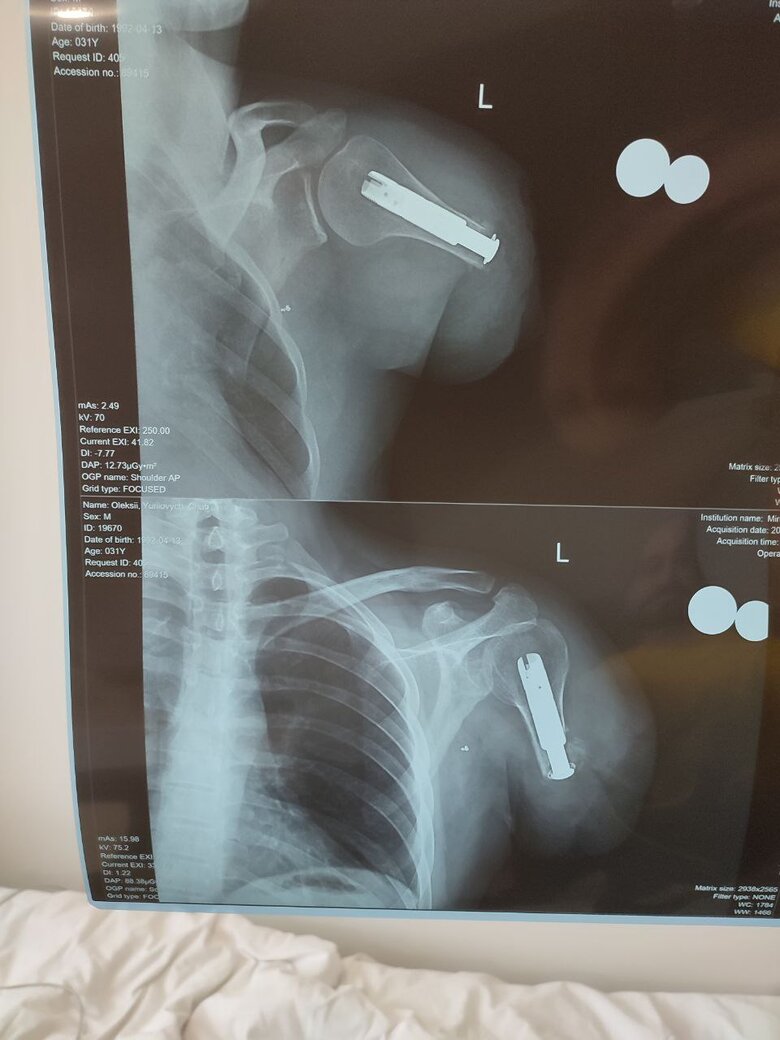

У лютому минулого року неподалік Бахмуту був поранений. Лікарям довелося ампутувати йому ліву руку до плеча. Уже змінив кілька лікарень. Ми зустрілися з Олексієм в одній із них на початку січня. Розказує мені, що перед Новим роком пройшов перший етап остеоінтеграції – операцію, під час якої в руку вживили імплант. Це один з тих, завдяки якому після ще одного подібного втручання можна буде кріпити протез. Потім його перевели до реабілітаційного центру, в який 2 січня під час обстрілу Києва влучила російська ракета. На щастя, не розірвалася й застрягла у підлозі. Пацієнтів евакуювали.

- У вас висока ампутація. Тепер ставлять імплант, далі протез чи як?

- Вставили перший імплант, який вживлений в кістку.

Він приживається приблизно два місяці. Операцію робив Рікард Бранемарк (шведський професор, видатний хірург-ортопед. – О.М.), який спеціально приїжджав сюди і прооперував кількох хлопців. Ми так між собою говоримо: він – Бред Пітт в хірургії (посміхається. – О.М.).

На другому етапі мені мають вкрутити ще один імплант – скажімо так, подовжувач. З руки стирчатиме металевий штирьок сантиметрів п’яти. Теж треба час, щоб прижився. Потім вживлюють датчики, а далі – біонічна рука з функціями звичайної.